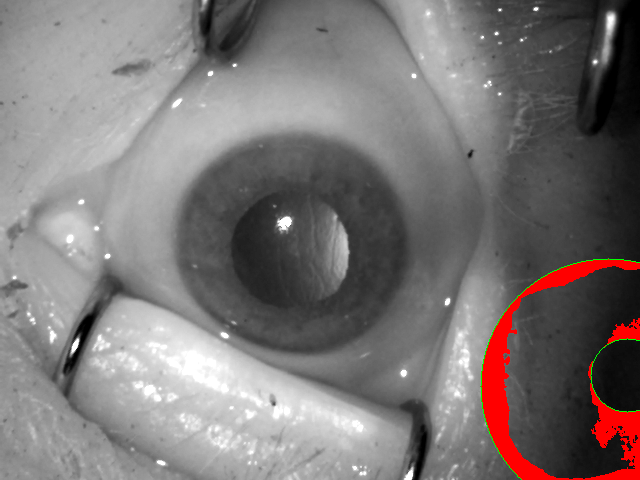

During data acquisition, we had the opportunity to collect images using two types of cameras: one producing near-infrared images of VGA size ( pixels), and the second producing color photographs of high resolution. Both near-infrared and visible-light images were used in visual inspection presented in Sec. IV-B. Using only red channel of color iris samples acquired in visible-light has been found to offer high recognition accuracy [31] even when being matched with near-infrared samples [32]. Thus, in this study, two types of samples are used: a) original near-infrared and compliant to ISO/IEC 19794-6 and ISO/IEC 29794-6 standards, and b) red channel of visible-light images manually center-cropped to conform the VGA image type, as defined in ISO/IEC 19794-6. Hence, the resolution of all images is pixels. This cropping of visible-light sample additionally protects the identity of donors, as original high-resolution visible-light images contained significant portions of face region. An example pair of near-infrared sample and the cropped red-channel image of the same eye is shown in Fig. 4.

V-B2 Manually-annotated ground-truth iris masks

The erroneous execution of the segmentation stage is usually a main cause of drops in iris recognition performance, when samples presented to the algorithms are of challenging nature. To test whether this is also the case for post-mortem data, we have taken the effort to prepare manually annotated iris masks for all of the iris images involved in this study, including both NIR and visible light samples, as depicted in Fig. 4.